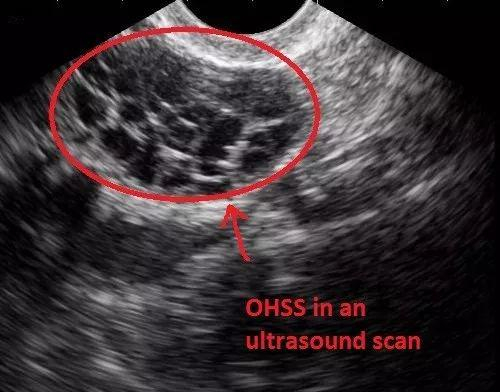

而情况严重者,还可能引起卵巢过度刺激综合征(Ovarian Hyper-Stimulation Syndrome, OHSS)。

自然周期下的卵巢;促排卵后的卵巢;卵巢过度刺激下的囊性增大

这是一种人体对促排卵药物产生的过度反应而引起的医源性疾病。

其主要临床表现为卵巢囊性增大、毛细血管通透性增加、体液积聚于组织间隙,引起腹腔积液、胸腔积液,伴局部或全身水肿。

卵巢过度刺激综合征的发生率 ,大约在5%之间,说高不高说低也不低。供卵者轻则腹痛呕吐,重则腹水、血栓、肾衰竭、中风乃至死亡。

超声下显示的卵巢过度刺激综合征

此外,促排卵过程还有1%的概率会发生卵巢扭转